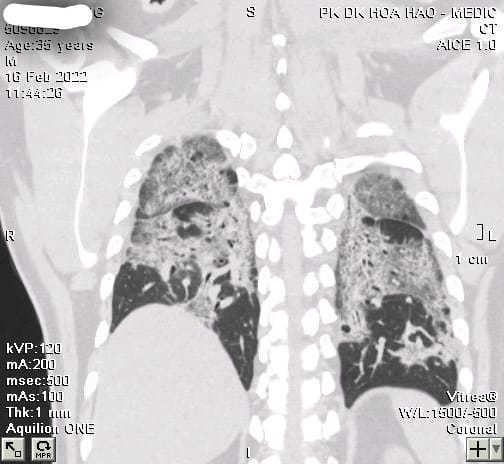

19/02/2022 18:26F0 không có triệu chứng, phổi vẫn trắng xoá hậu Covid-19

Trên Infonet, bác sĩ Phan Xuân Trung – Trung tâm Y tế Hoà Hảo, TP.HCM cho biết thời gian qua người bệnh di chứng hậu Covid-19 đi kiểm tra ngày càng tăng. BS Trung từng tiếp nhận các trường hợp bị xơ phổi diễn tiến thậm chí người bệnh trẻ khi mắc Covid-19 không có triệu chứng nhưng khi khỏi bệnh thì phổi lại xơ dần.

Trường hợp nam bệnh nhân tên N.N.V. 35 tuổi, mắc Covid-19 do lây từ vợ. Người bệnh đã tiêm hai mũi vắc xin và khi nhiễm bệnh không có triệu chứng nên điều trị tại nhà.

Sau điều trị Covid-19, bệnh nhân lại rơi vào tình trạng hậu Covid-19 thường xuyên thấy khó thở, đi lại cũng mệt, lúc nào cũng thấy “ngộp”. Bệnh nhân tới kiểm tra sức khoẻ, bác sĩ cho chụp phổi để đánh giá tổn thương phổi thì hết sức bất ngờ vì phổi của bệnh nhân trắng xoá do tình trạng xơ phổi diễn tiến.